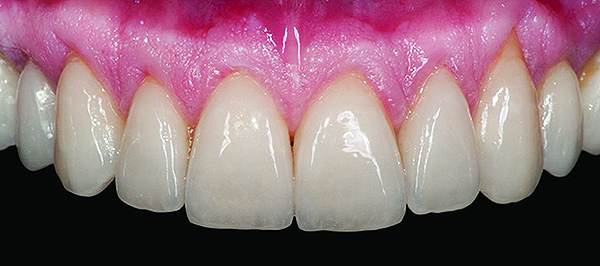

Fig 3. Preoperative (Fig 1), preparation (Fig 2), and final postoperative (Fig 3) images of a two-unit CL-I feldspathic veneer case.

Figure 3